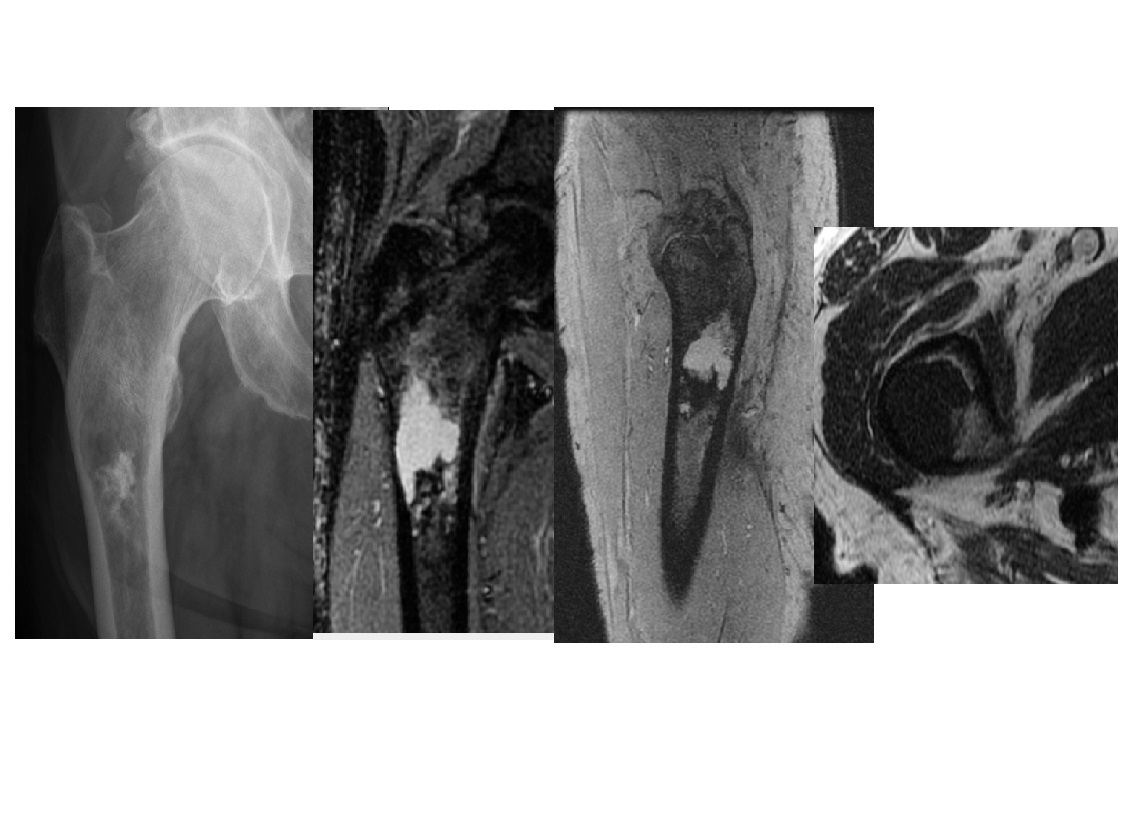

Chondrosarcoma

May be cecondary to

- Osteochondromas

- enchondromas

Chondrosarcomas occur in the pelvis, femur, humerus.

Skull base, TMJ

DDX

-Most well differentiated, low grade = ‘low grade chondroid lesion’ , cant differentate from enchondroma

-Bone infarct

MRI

Lobular growth

High 2 signal/STIR, low T1

ring and arcs/chondroid matrix islands on CT

Soft tissue extension

**endosteal scalloping. **

if no mineralized matrix/rings and arcs = aggressive/high grade

How to tell chondrosarcoma from enchondroma ?

* Pathological fracture occurring with minimal trauma

* Multilayered or spiculate periosteal reaction

* Permeative or moth-eaten osteolysis

* Cortical destruction

* A soft tissue mass

Endosteal scalloping more than 2/3 cortex